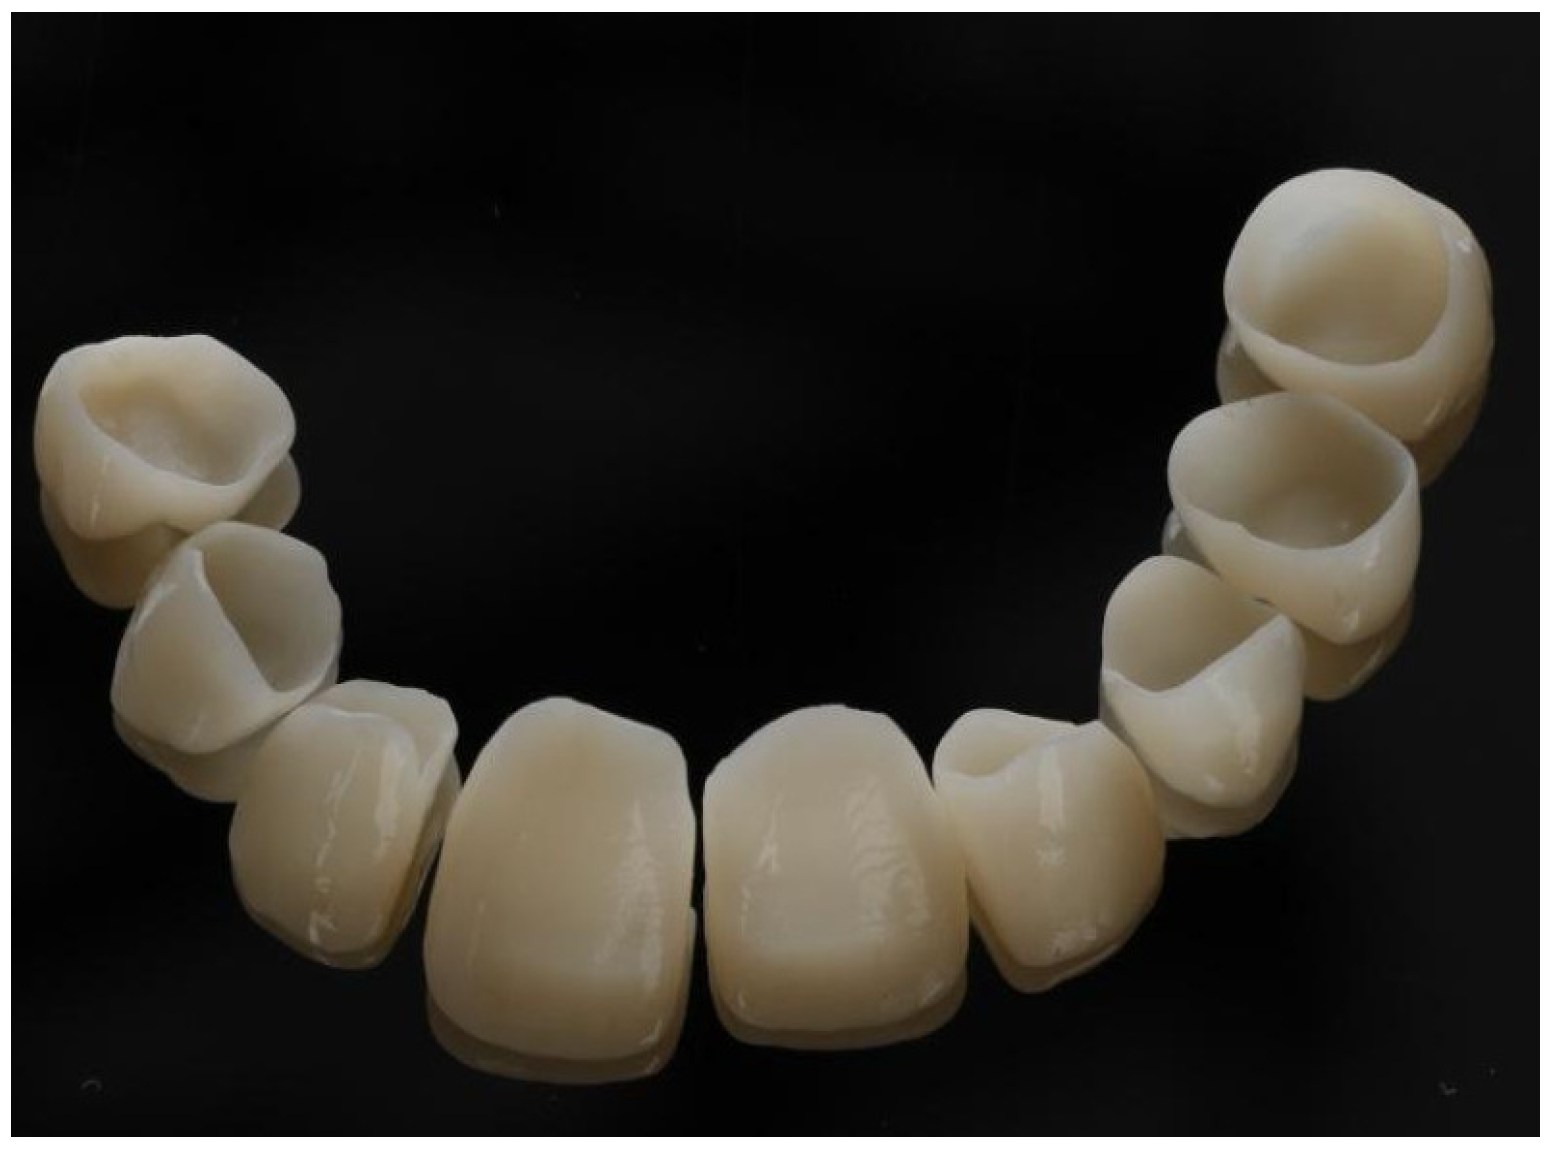

2. Case Report